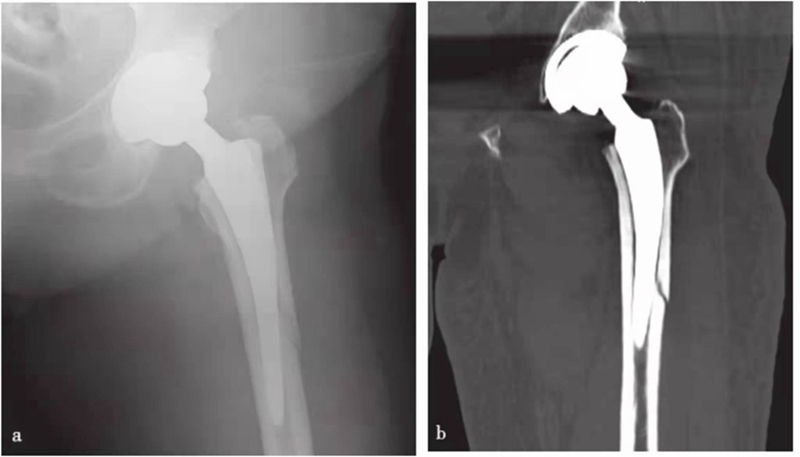

图15 人工关节置换术后股骨干骨折

a. X线片;b. CT冠状位重建,示左侧假体柄远端附近股骨干骨折